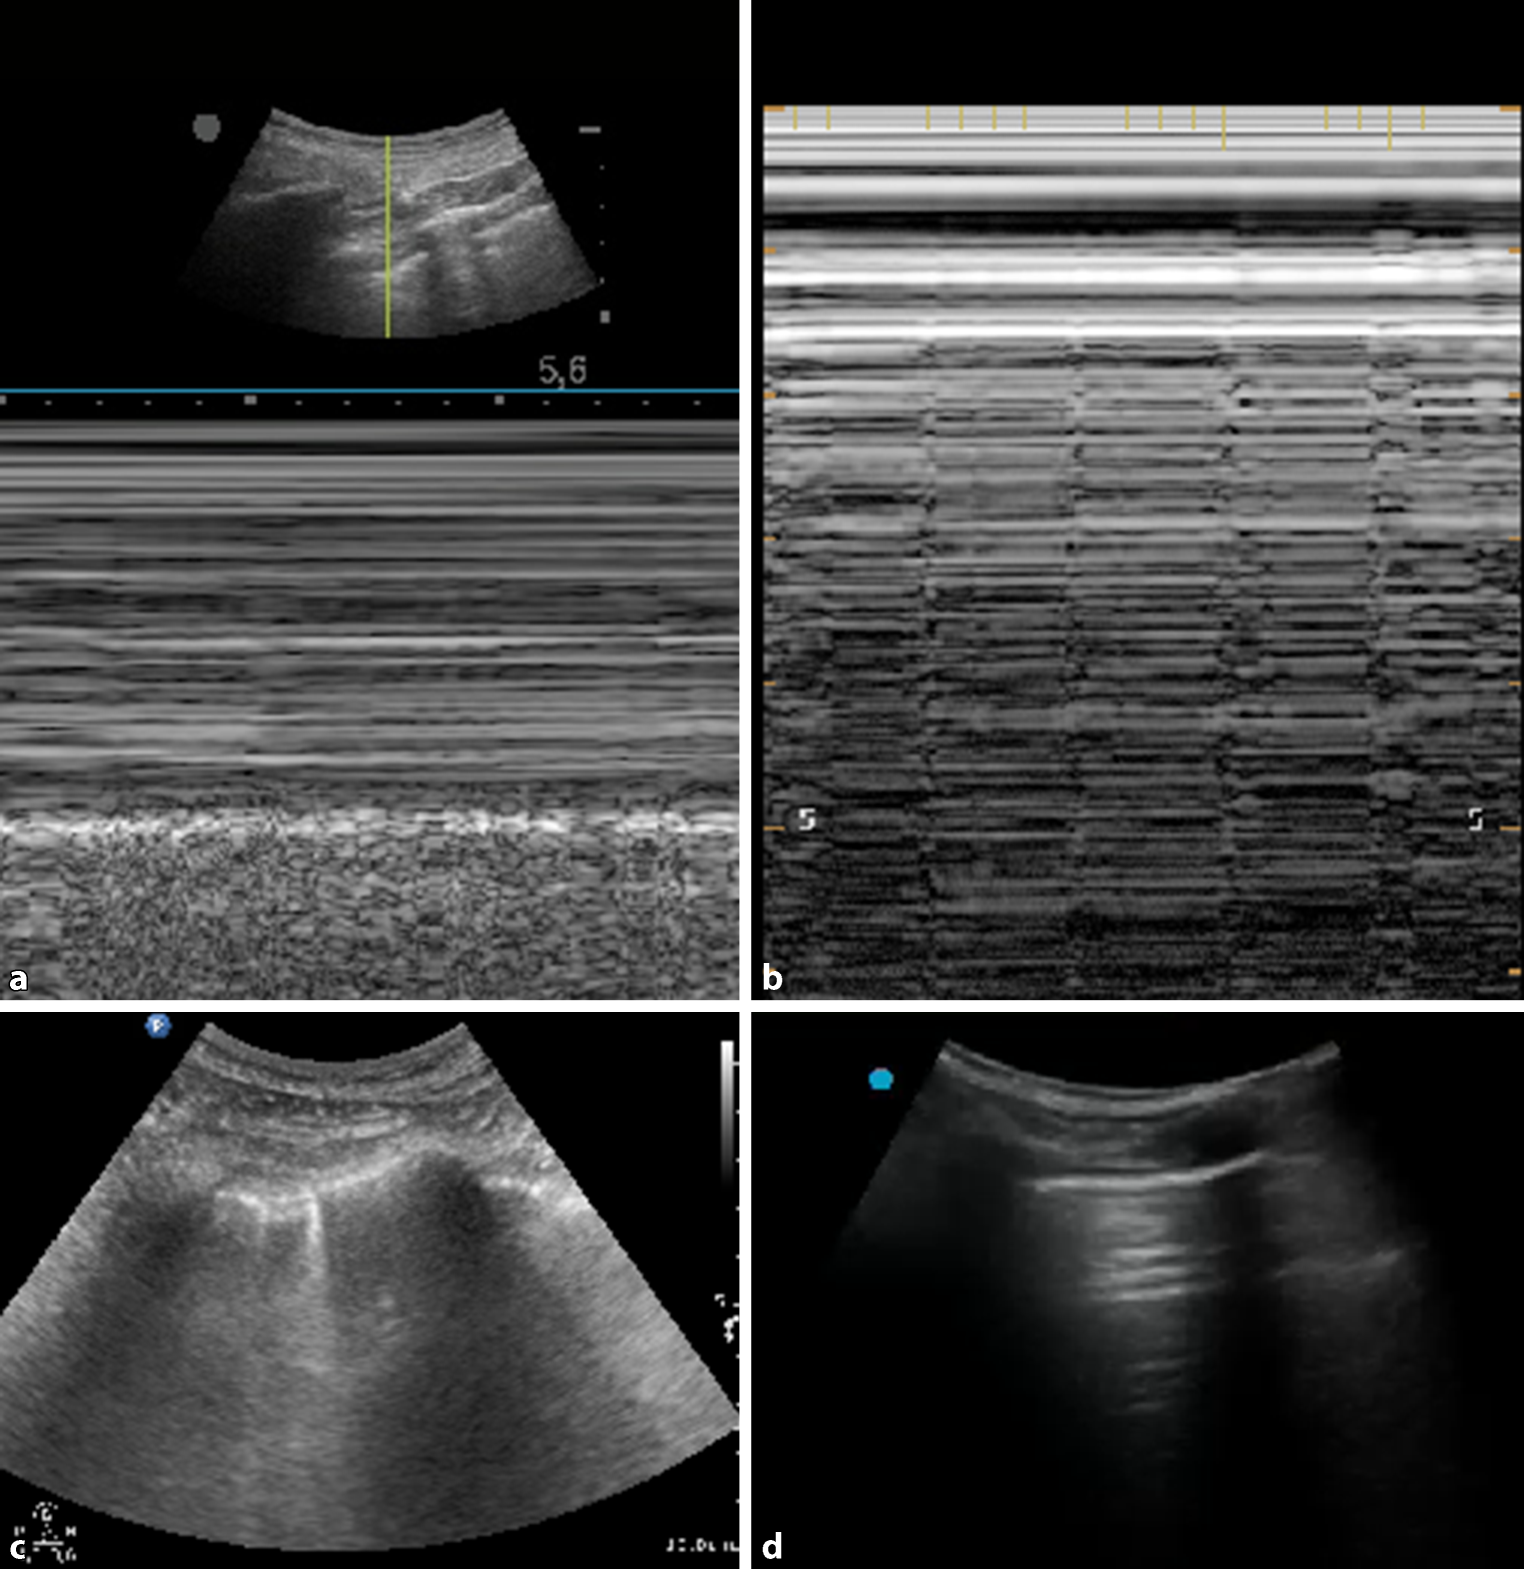

Fig. 2

Important sonographic signs; for detailed explanations, please read [10, 11]. a Lung sliding, represented by the seashore sign in M‑mode, rules out pneumothorax. Lung sliding is abolished in pneumothorax, but also in severe emphysema, fibrosis, pleural adhesions, for instance; therefore, abolished lung sliding is not diagnostic for pneumothorax. b Lung pulse, pulse synchronous vertical lines which end with the pleural line, rules out pneumothorax. c Two B‑lines, rising from interstitial fluids at the pleural line, sharp, laser-like, rule out pneumothorax. d Multiple A‑lines, i.e. horizontal repetitions of the pleural line. This sign occurs in healthy subjects as well as in lung emphysema and pneumothorax. Thus, A‑lines must be interpreted only in combination with further signs